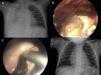

A) Radiografía de tórax en la que se observa una cavidad con nivel hidroaéreo en su interior en hemitórax derecho. B) La TAC preoperatoria muestra lesión compatible con neumonía necrosante abscesificada de lóbulo inferior derecho. C) Imagen intraoperatoria del absceso pulmonar; nótese el aspecto verdoso del parénquima y las burbujas de aire a su alrededor causadas por la FBP. D) Control radiológico a los 2 meses de la cirugía.

A) Radiografía de tórax preoperatoria con empiema derecho que llega hasta el ápex pulmonar. B) Imagen toracoscópica en la que se aprecia la salida del contenido del absceso. C) Imagen intraoperatoria de la cavidad del absceso tras la evacuación de los detritus. D) Control radiológico a los 2 meses de la cirugía.